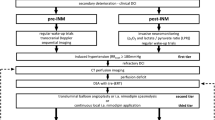

Between January 2012 and August 2014 (pre-implementation cohort), there was no multidisciplinary consented protocol for the management of aSAH patients, who were admitted to our department. Management decisions were usually taken by the treating neurosurgeon or neuroradiologist on an individual basis, and patients were predominately treated according to the presence of angiographic vasospasm. In retrospect, the management in the pre-implementation cohort may be summarized as follows: Patients were (A) neurologically assessed in the intensive or intermediate care unit during daily rounds by neurosurgical residents and staff and (B) underwent digital subtraction angiography on days 6 to 9 after aneurysm repair or immediately upon clinical deterioration for the assessment of the presence of angiographic vasospasm (Figs. 1 and 2a). Clinical deterioration was defined as a new neurological deficit (aphasia and/or paresis) or a decline in consciousness. Angiographic vasospasm was regarded as clinically relevant in case of clinical deterioration suggestive of DCI or evidence of new hypodensities on unenhanced CT scans. Induced hypertension, if at all, was not consistently applied and was not part of a tailored and escalating treatment approach. Patients with severe, progressive, or clinically relevant vasospasm received an intra-arterial catheter for continuous nimodipine administration as first-line treatment. Angiographic vasospasm was monitored by a follow-up digital subtraction angiography after 72 h.

Clinical and radiological DCI monitoring and screening protocol. Abbreviations: CCT, cranial computed tomography; CTA, CT-angiography; DSA, digital subtraction angiography; i.a., intra-arterial; MTT, mean transit time; Neuro exam, neurological examination every 2 h; PCT, CT perfusion; SAH, subarachnoid hemorrhage

Algorithms for the management of patients with DCI. A DCI management algorithm in the pre-implementation cohort. B Escalating treatment protocol for patients with DCI in the post-implementation cohort. Abbreviations: CCT, cranial computed tomography; DSA, digital subtraction angiography; i.a., intra-arterial; MTT, mean transit time; PCT, perfusion computed tomography

In fall 2015, the authors (NE, CG, ENP, JK) developed and implemented an interdisciplinary protocol for standardized detection and management of DCI (see below) in line with their previously reported studies [6, 10]. Following a transition period, from January 2016 onward, all aSAH patients admitted to our department (post-implementation cohort) were routinely discussed in a multidisciplinary team of neurosurgeons, neuroradiologists, and intensive care specialists, and management decisions in case of deterioration were taken based on the protocol and multidisciplinary discussion. The standardized detection protocol included thorough neurological examinations every 2–4 h by dedicated neurocritical care residents in combination with a novel CT perfusion screening protocol (Fig. 1). CT perfusion measurements were performed 6–12 h after aneurysm treatment, on days 3 or 4 as well as days 9 to 11 after aSAH, or in case of clinical features of DCI [6, 10, 17]. For patients who were and remained in perfect condition, the last CT perfusion was omitted. Additionally, digital subtraction angiographies were performed on admission and on days 6 to 9 after aSAH ictus and in case of clinical deterioration from DCI or CT perfusion deficits. In the case of persistent clinical signs of DCI, severe CT perfusion impairment or severe angiographic vasospasm, the patients in the post-implementation cohort were treated by means of a standardized, escalating treatment protocol: First, induced hypertension with a targeted systolic blood pressure of > 180 mmHg; second, solitary intra-arterial nimodipine bolus applications during catheter angiography; and third angiographic application of an intra-arterial catheter for continuous nimodipine administration over 48 h with CT perfusion imaging in between each escalating step (Fig. 2b).